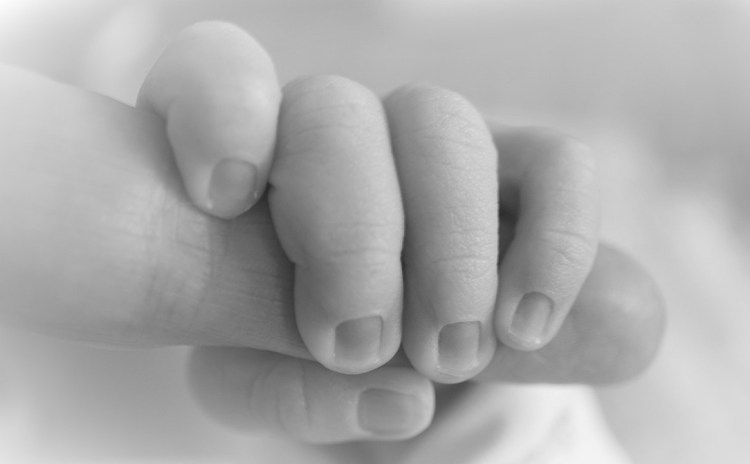

CONSULTA MÉDICA SUBESPECIALIZADA EN CIRUGÍA DE LA MANO EN NIÑOS Y ADULTOS

El movimiento de nuestras manos es fundamental en el día a día, preservar la misma y mejorar su función es nuestro compromiso.

DIAGNÓSTICO Y TRATAMIENTO DE ENFERMEDADES CONGÉNITAS DE LA MANO EN NIÑOS

Del 1 al 3% de los niños, presentan alguna malformación al nacer y el 10% de las mismas afecta el sistema musculoesquelético, la más frecuente es la Sindactilia (fusión de dos o más dedos) la cual puede tratarse con cirugía y así brindar la función adecuada a la mano en los niños.